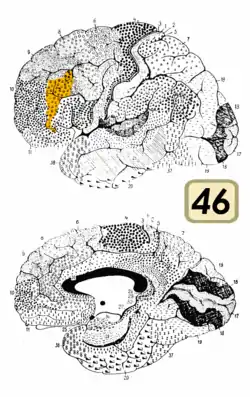

Brodmann area 46, or BA46, is part of the frontal cortex in the human brain. It is between BA10 and BA45.

BA46 is known as middle frontal area 46. In the human brain it occupies approximately the middle third of the middle frontal gyrus and the most rostral portion of the inferior frontal gyrus. Brodmann area 46 roughly corresponds with the dorsolateral prefrontal cortex (DLPFC), although the borders of area 46 are based on cytoarchitecture rather than function. The DLPFC also encompasses part of granular frontal area 9, directly adjacent on the dorsal surface of the cortex.

Cytoarchitecturally, BA46 is bounded dorsally by the granular frontal area 9, rostroventrally by the frontopolar area 10 and caudally by the triangular area 45 (Brodmann-1909). There is some discrepancy between the extent of BA8 (Brodmann-1905) and the same area as described by Walker (1940).[1]

Lateral view.